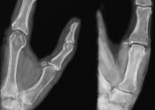

Archives de Catégorie: La main pathologique

Luxations proximales de la main : semi-lunaire, périlunaire, carpo-métacarpienne

Luxation du semi-lunaire et périlunaire Luxation carpo-métacarpienne Références Médias Luxation du semi-lunaire et périlunaire Survient chez les patients jeunes pour des traumatismes violents (AVP et chutes de lieu élevé). La … Lire la suite

Fracture du métacarpien du pouce : Bennett et Rolando

Les fractures de Bennett et Rolando sont des fractures de la base du pouce, du 1er métacarpien donc. Ces fractures tirent leur nom d’Edward Hallaran Bennett (1837-1907), chirurgien irlandais, et Silvio Rolando, un chirurgien italien (dont … Lire la suite